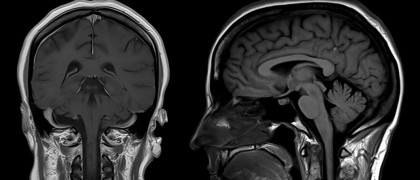

În interiorul neuronilor, receptorii de rianodină defecți au fost anterior legați de o creștere a proteinei tau fosforilat, un semn distinctiv binecunoscut al bolii Alzheimer. În noul studiu, cercetătorii de la Columbia au descoperit niveluri ridicate de tau fosforilat în creierul pacienților cu COVID-19, în plus față de receptorii de rianodină defecți. Tau fosforilat a fost găsit în zonele în care tau este de obicei localizat la pacienții cu Alzheimer, precum și în zonele în care nu este de obicei localizat la pacienții cu Alzheimer, lucru care sugerează că tau fosforilat la pacienții cu COVID-19 ar putea fi un semn al bolii Alzheimer în stadiu incipient și, de asemenea, poate contribui la alte simptome neurologice observate la pacienții cu COVID-19.

Pe baza constatărilor, împreună cu modificări suplimentare găsite în creier, anchetatorii teoretizează că răspunsul imun caracteristic COVID-19 sever provoacă inflamația în creier, care, la rândul său, duce la pierderea funcției receptorilor de rianodină.